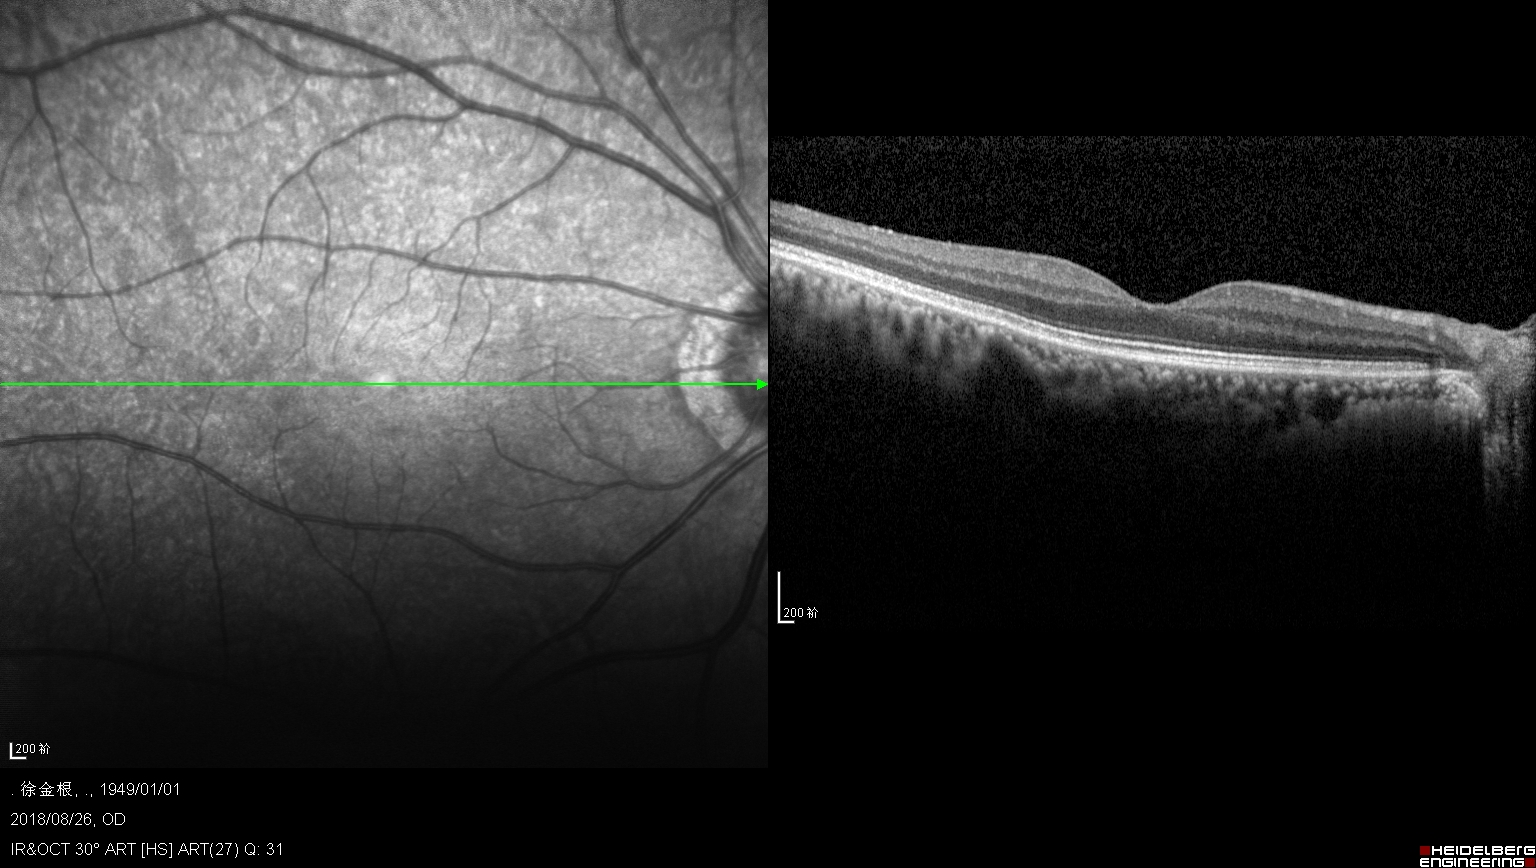

右眼黄斑裂孔,上方可以看见被牵拉掉的组织

潘阿姨双眼所患的是:“黄斑牵引综合征”,左眼可以看见黄斑区的视网膜被玻璃体牵拉水肿,即将出现黄斑裂孔,而右眼已经是个全层的黄斑裂孔,在黄斑的上方可以看见被牵拉掉的视网膜组织。。